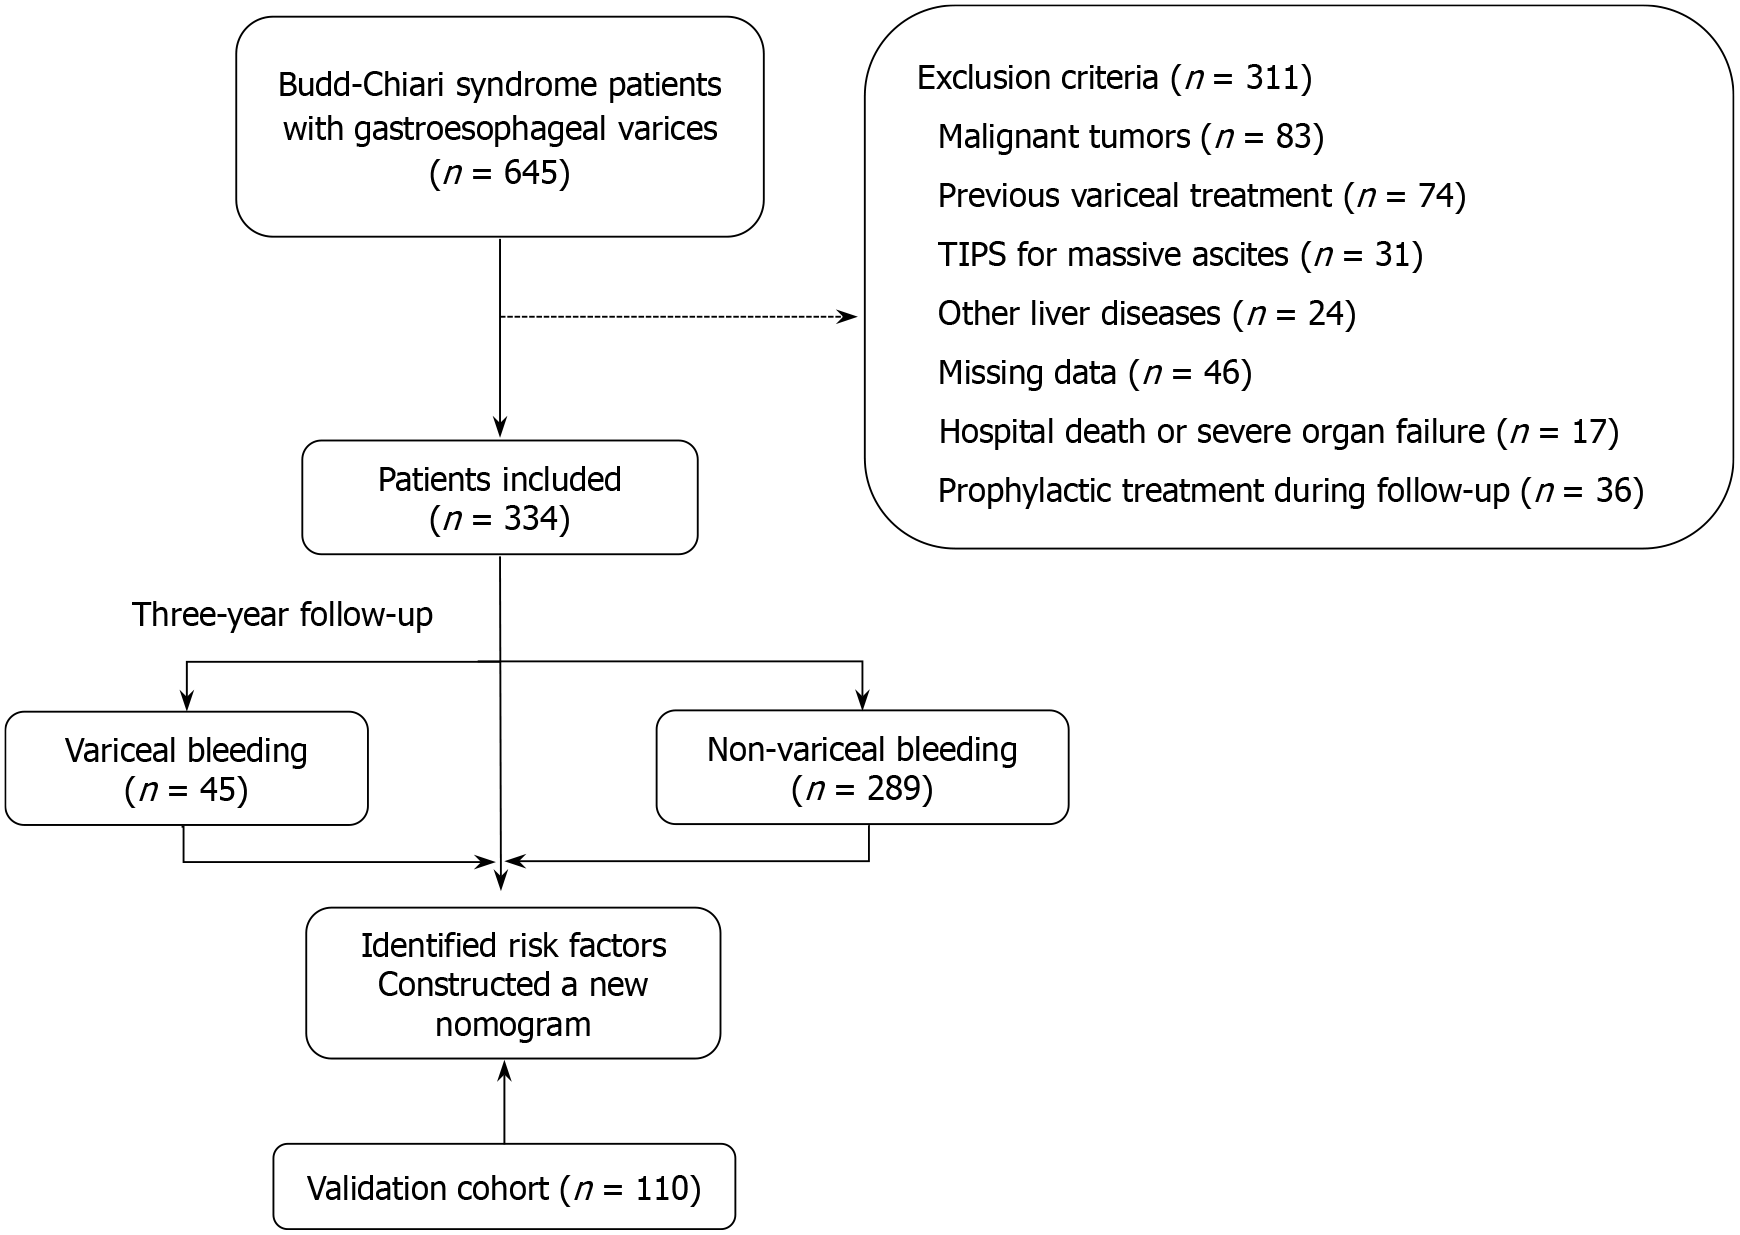

Participants were included if they met the following criteria: (1) Definitive diagnosis of BCS based on imaging evidence of venous outflow obstruction; and (2) First-time diagnosis of GEVs based on three-phase enhanced CT imaging. Patients were excluded if they met any of the following criteria: (1) Previous variceal treatment; (2) Presence of malignant tumors; (3) Other liver diseases such as viral, alcoholic or autoimmune hepatitis; (4) Incomplete or poor-quality imaging or clinical data; (5) In-hospital death or concurrent severe organ dysfunction; (6) Transjugular intrahepatic portosystemic shunt (TIPS) for massive ascites; or (7) Prophylactic treatment for GEVs during follow-up. The inclusion and exclusion process is summarized in Figure 1.

A total of 444 BCS patients with GEVs were included in this study. The mean age of the cohort was 51.5 ± 10.9 years (range 21-85 years), and 58.9% were male. During the follow-up period, 61 patients (13.7%) experienced their first variceal bleeding event. Patients were classified into the bleeding group (n = 61) and the nonbleeding group (n = 383). A comparison of baseline characteristics between the two groups is presented in Table 1.

To develop and validate the risk prediction model, patients from the First Affiliated Hospital of Zhengzhou University (n = 334) were designated as the training cohort, whereas those from Zhengzhou University People’s Hospital (n = 110) constituted the validation cohort. There were no significant differences (all P > 0.05) in baseline demographics, clinical parameters or imaging findings between these two cohorts (Table 2). Such comparability ensures a robust basis for subsequent model development and external validation.